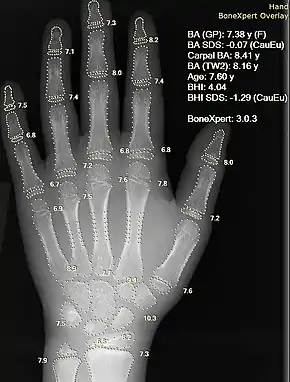

Plain radiography was the only imaging modality available during the first 50 years of radiology. Due to its availability, speed, and lower costs compared to other modalities, radiography is often the first-line test of choice in radiologic diagnosis. Also despite the large amount of data in CT scans, MR scans and other digital-based imaging, there are many disease entities in which the classic diagnosis is obtained by plain radiographs. Examples include various types of arthritis and pneumonia, bone tumors (especially benign bone tumors), fractures, congenital skeletal anomalies, and certain kidney stones.

Mammography and DXA are two applications of low energy projectional radiography, used for the evaluation for breast cancer and osteoporosis, respectively.